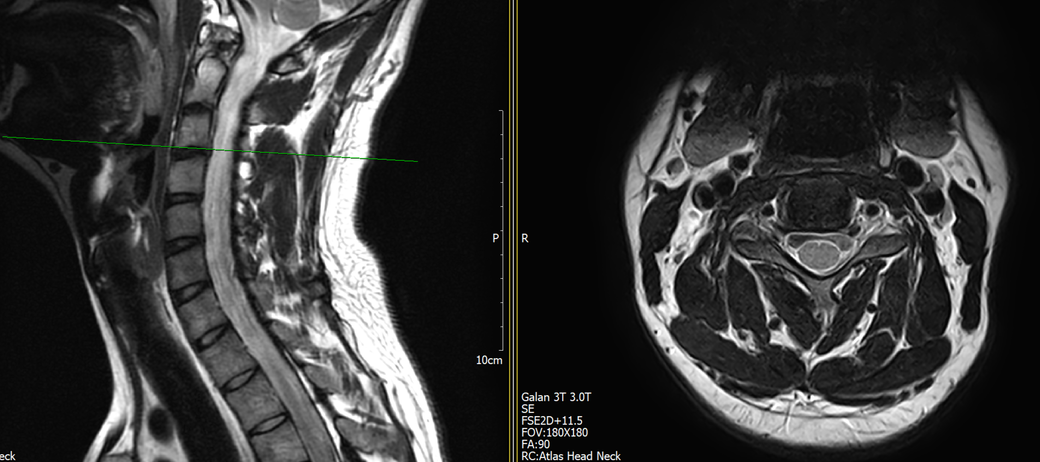

목과 오른쪽 어께 통증이 있어 mri를 찍어왔는데, 사진에서 의심되는 부분 있을까요?

• 2번 째 사진

MRI만 보면 굉장히 깨끗한 목입니다.

디스크탈출은 없고 신경뿌리가 압박될만한 모습도 전혀 보이지 않습니다.

지금은 MRI에서 잘 보이지 않는 디스크내장증일 가능성이 높아보이며 경추전만 자세를 잘 유지해주시는게 가장 큰 도움이 되겟습니다.